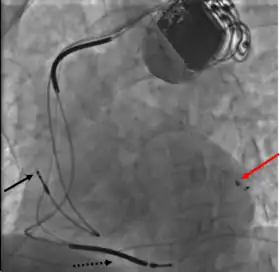

A venipuncture is made, and a guide wire inserted into the vein, where it is guided, with use of real time X-ray imaging, through to the right ventricle. The guide wire is then used to assist in the placement of the electrode lead, which travels through the venous system into the right ventricle where the electrode is embedded.[1]

This is generally performed subsequent to RV lead placement, with the RV lead providing a backup in case of accidental damage to the electric fibers of the heart, causing an asystolic event. As with the RV lead, a guide wire is first inserted, allowing for the insertion of a multi-delivery catheter. The catheter is subsequently maneuvered to the opening of the coronary sinus in the right atrium. From here a contrast media is injected, allowing the surgical team to obtain a coronary sinus phleobogram to direct the placement of the lead into the most suitable coronary vein.[1]

Once the phlebogram has been obtained, the multi-delivery catheter is used to guide in the lead, from the chosen vein of entry, into the right atrium, through the coronary sinus and into the relevant cardiac vein.[1]